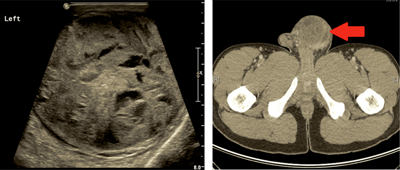

Testicular ultrasound is the imaging modality of choice to assess a testicular mass or swelling as it is sensitive, inexpensive and non-invasive. A CT scan of the chest, abdomen and pelvis with intravenous contrast to assess the retroperitoneum and mediastinum for pathological lymphadenopathy is standard. Fluorodeoxyglucose-positron emission tomography (FDG-PET) has failed to show any benefit over CT scan for initial staging of TC [3].

Figure 2: Ultrasound images demonstrating an enlarged left testicle with presence of heterogeneous mass which is re-demonstrated on axial cross-sections of an abdomen-pelvic CT scan in a patient with non-seminoma GCT.